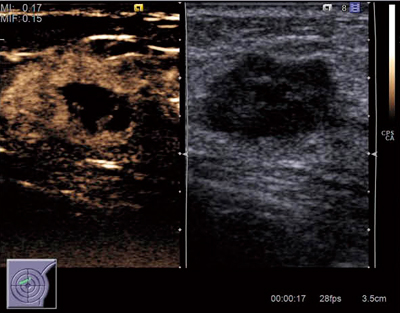

図4 CPSによる造影エコーの例

浸潤性微小乳頭がん

(画像ご提供:聖マリアンナ医科大学・桜井正児先生)